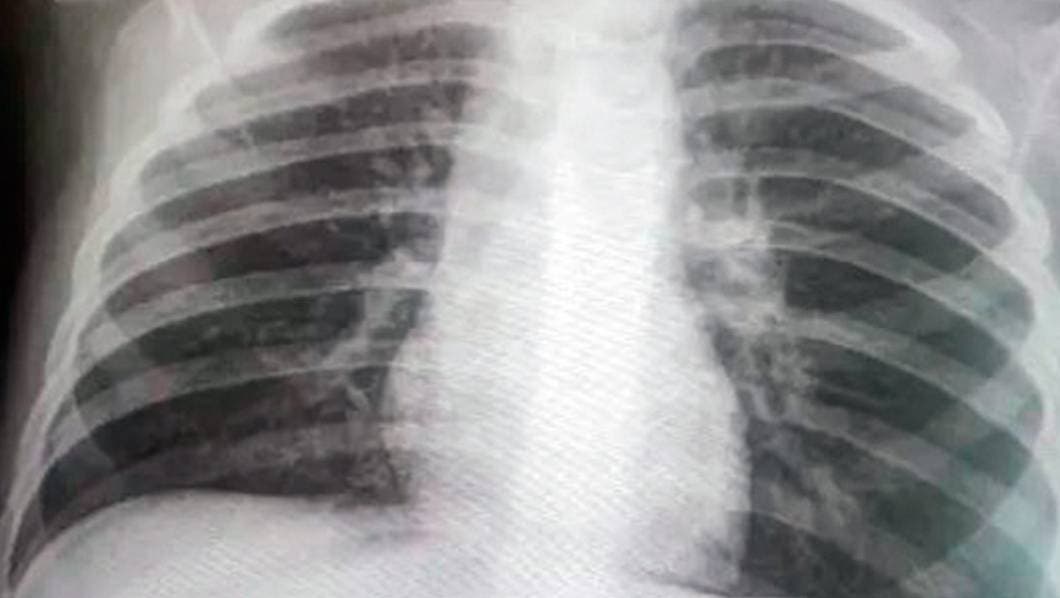

Cuernavaca, MORELOS.- Autoridades municipales indican que han aumentado los fallecimientos por “neumonías atípicas”, por lo que consideran que no coinciden las cifras de contagios por COVID-19 que informan autoridades de Salud estatal y federal.

“En el registro civil se han registrado muchas defunciones por neumonías atípicas o por cuestiones relacionadas; contabilizando sería la tercera causa de decesos que se registran actualmente”, declaró. iCumplen